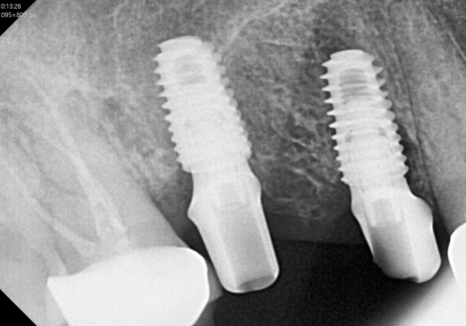

결국 뿌리 끝까지 염증이 퍼져

치아가 흔들리고 있었기에,

안타깝게도 이 치아는 살리기가 어려워

발치 후 뼈이식을 동반한 임플란트를

진행하게 되었습니다.